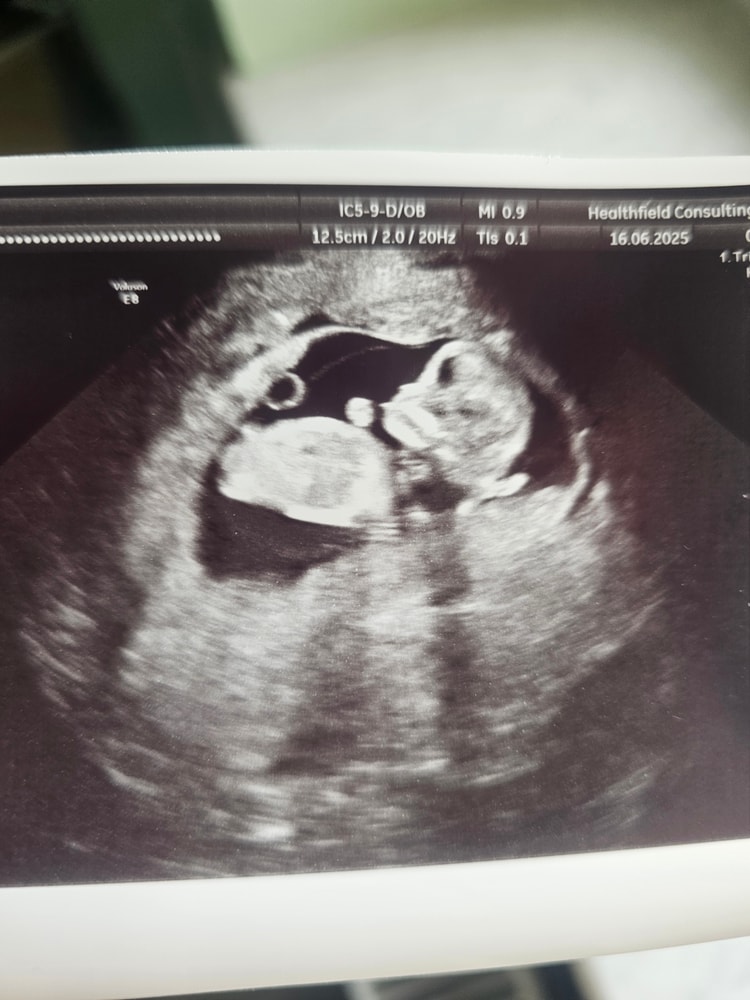

Пол малышаДевочки, всем привет. Сегодня на руки дали фото узи. Кто также от любопытства пытался определить пол по углу наклона? Совпадало ли у вас? Как думаете на фото мальчик/девочка?

Угол наклона точно такой же как у вас на снимке был, узист сказала что девочка)